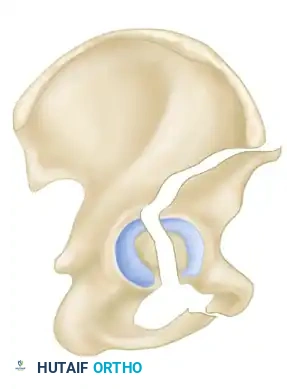

Secondary Congruence in Both-Column Fractures

A unique phenomenon observed exclusively in both-column fractures is "secondary congruence." Because all articular fragments are detached from the axial skeleton, they can occasionally settle concentrically around the medially displaced femoral head.

If the articular cartilage space is preserved and the femoral head remains concentrically enveloped by the fragments (despite medialization of the entire joint complex), nonoperative treatment via skeletal traction can yield surprisingly excellent long-term functional results.